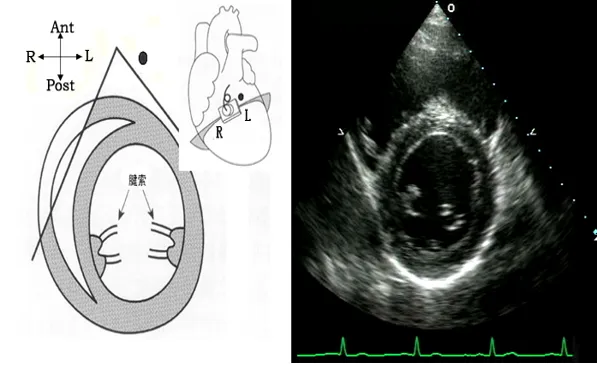

07

胸骨旁心尖水平短轴切面

● 探头位置:探头置于胸骨左缘3、4肋间,声速朝向心尖。

● 观察内容:心尖室壁厚度、心尖室壁运动。